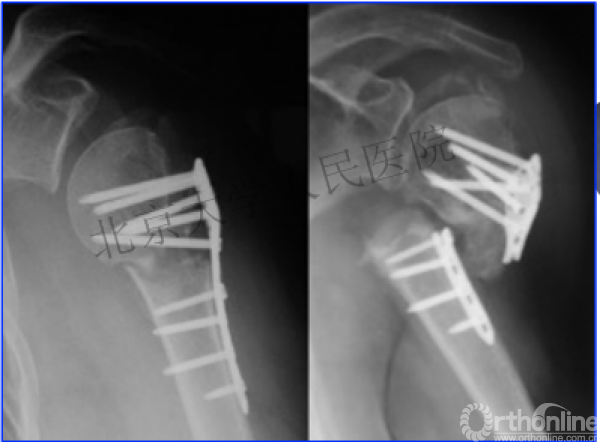

另一个留有遗憾的病例,您的选择?PHN?

临床中的广泛内固定治疗不断地提出思考